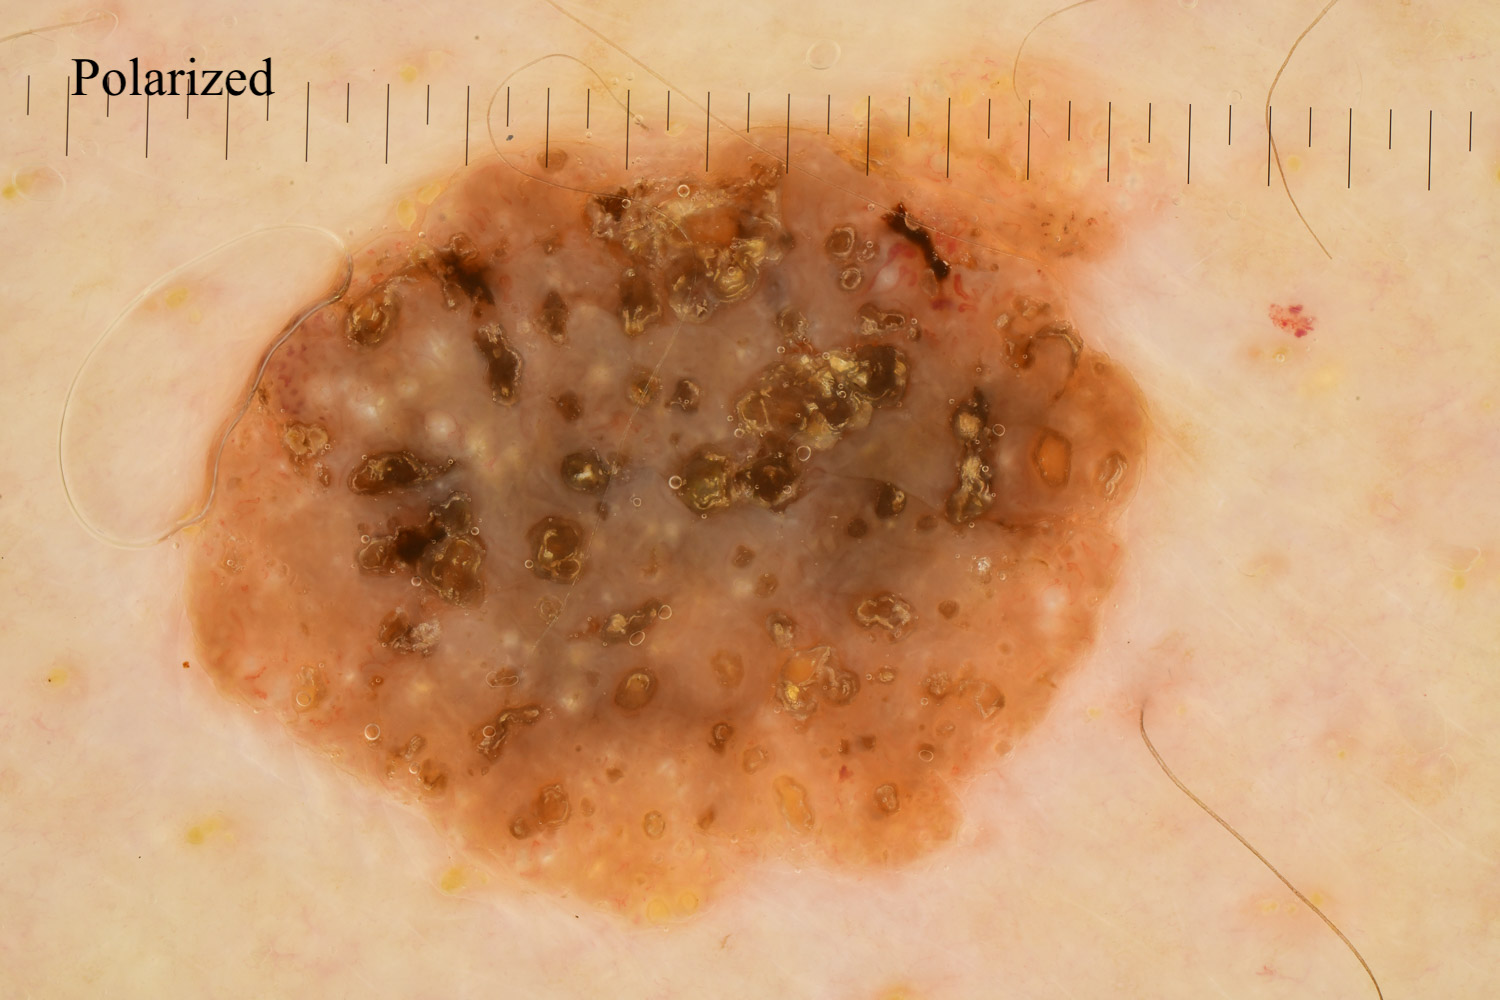

Case: 186